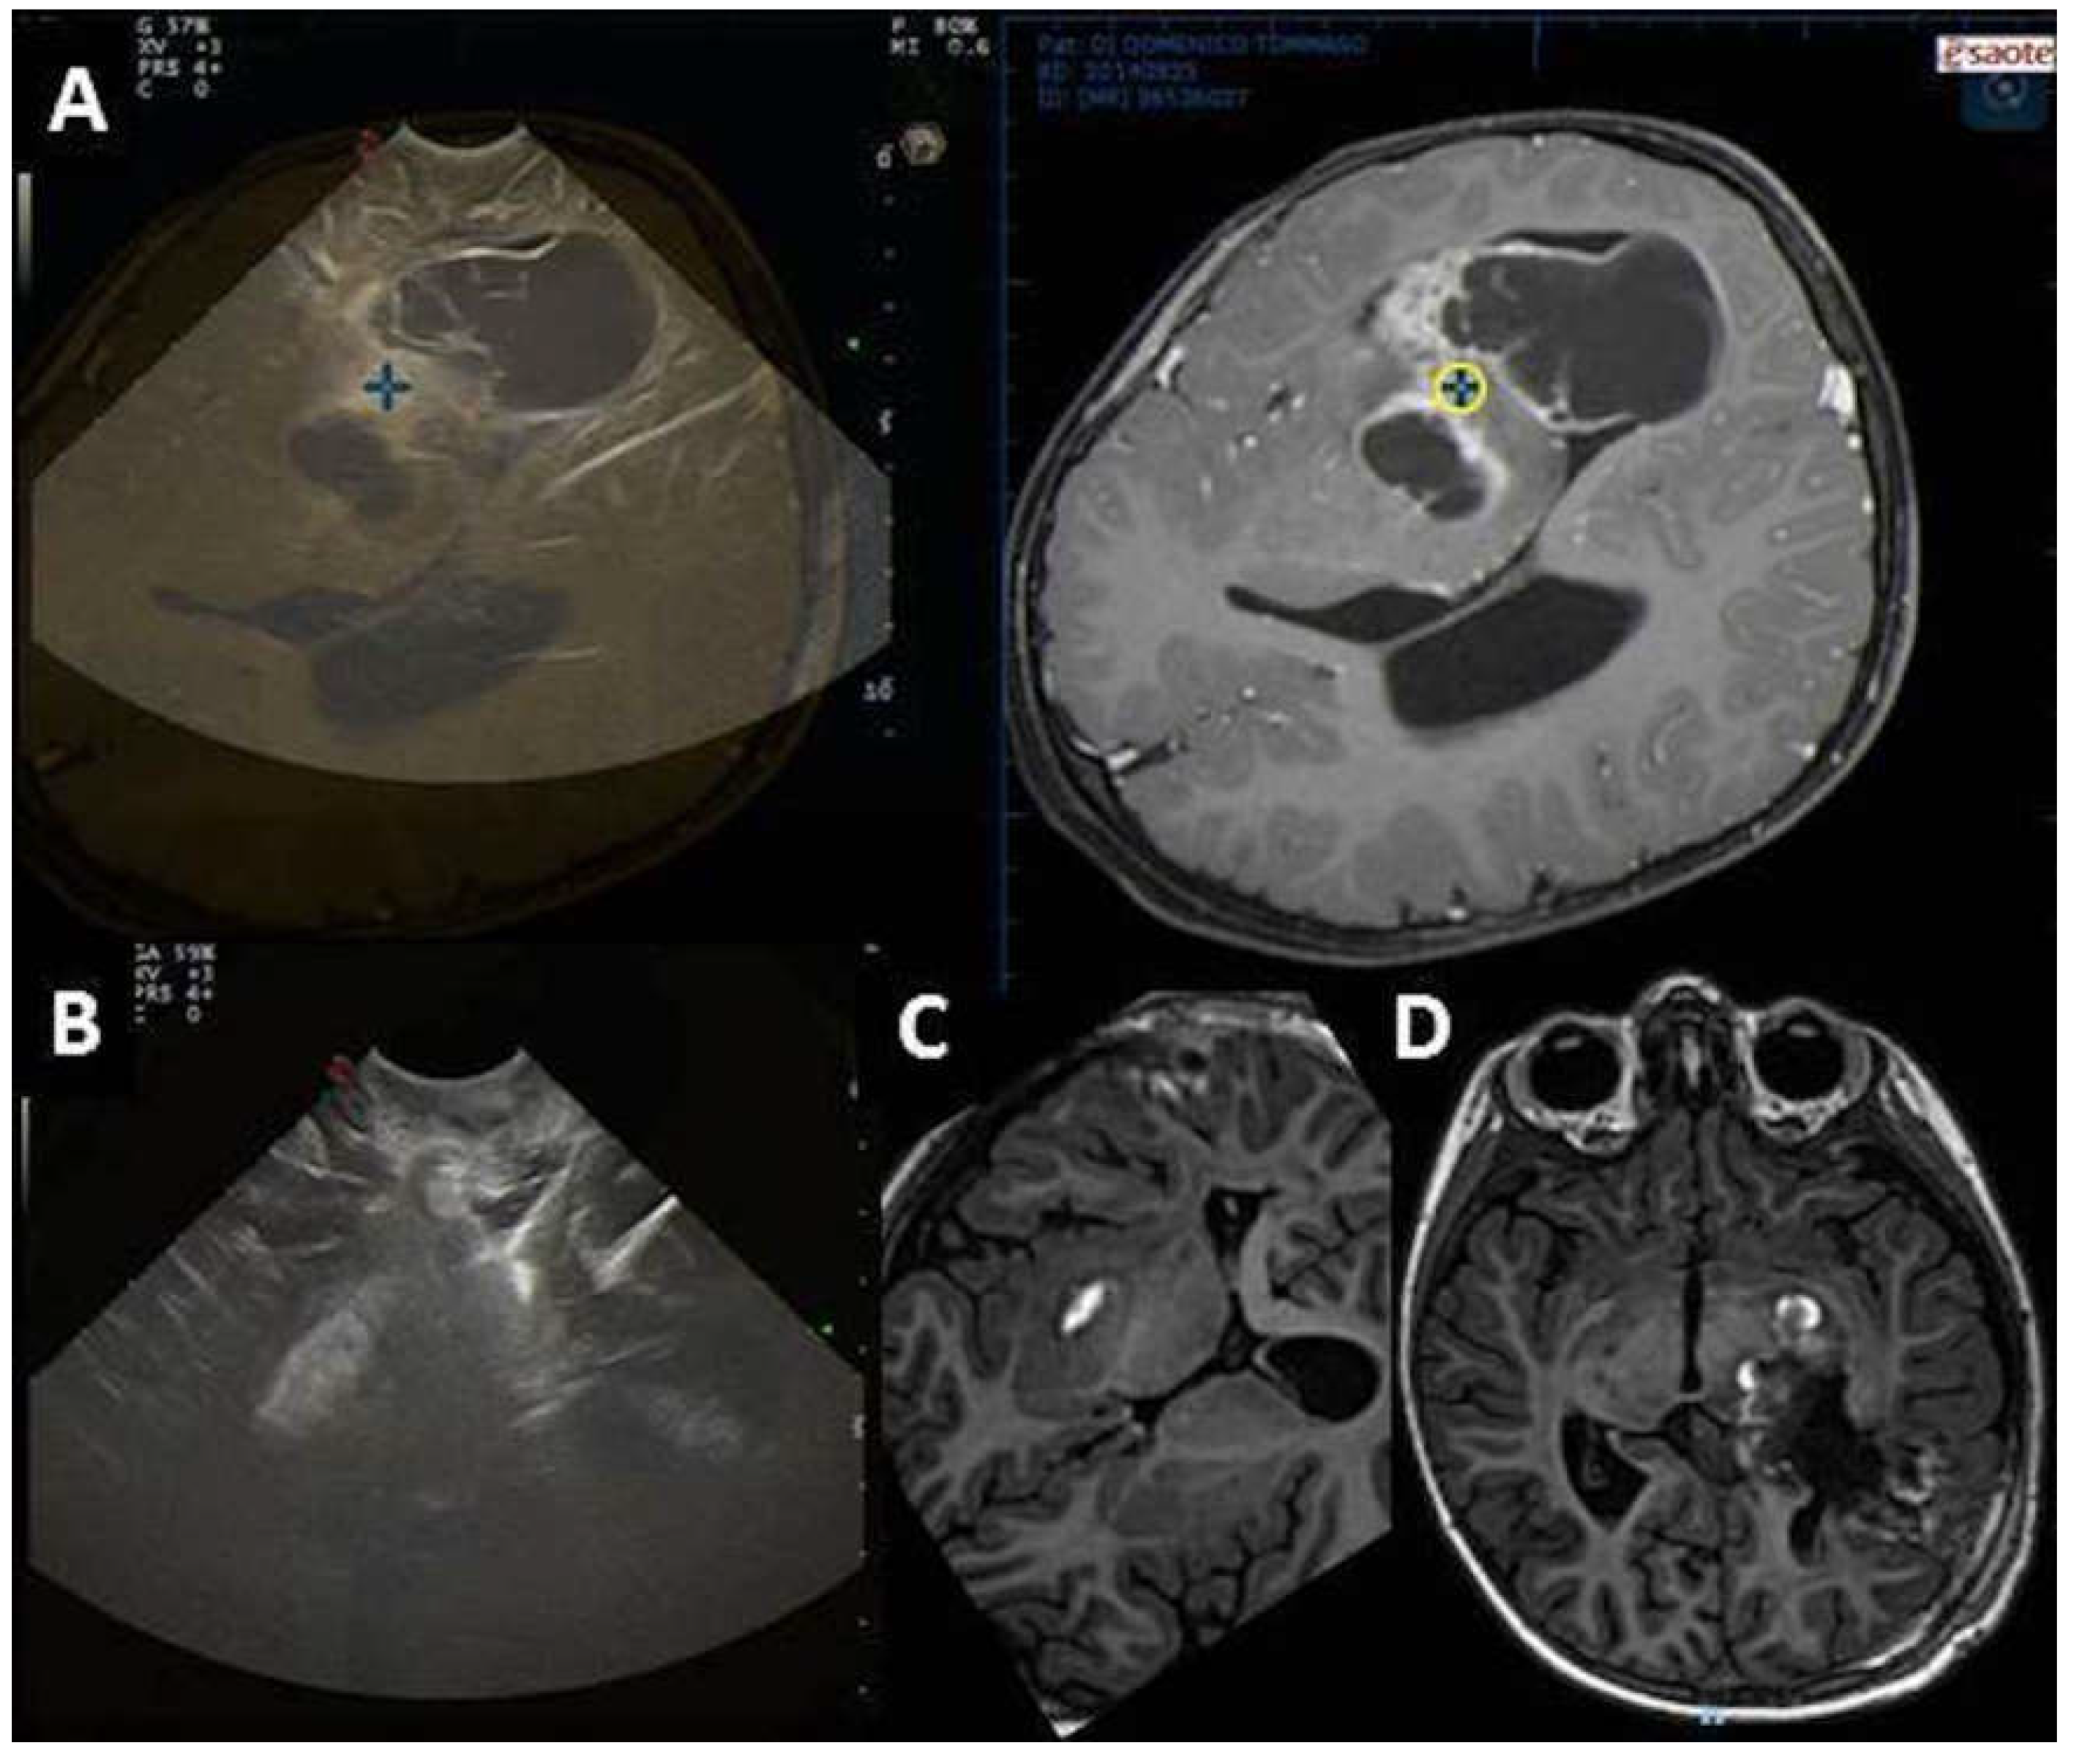

| Pre-IOUS | Problems | Solutions |

| Localization | Deep-seated lesion |

| Localization | Superficial lesion not distinguishable from brain parenchyma |

| Definition | Vascular relationship |

| Definition | Vascular pattern |

| Surgical route | Deep-seated lesion |

| Post-IOUS | ||

| EOR | Collapsed surgical cavity |

|

| EOR | Open ventricle |

| EOR | Artifacts |